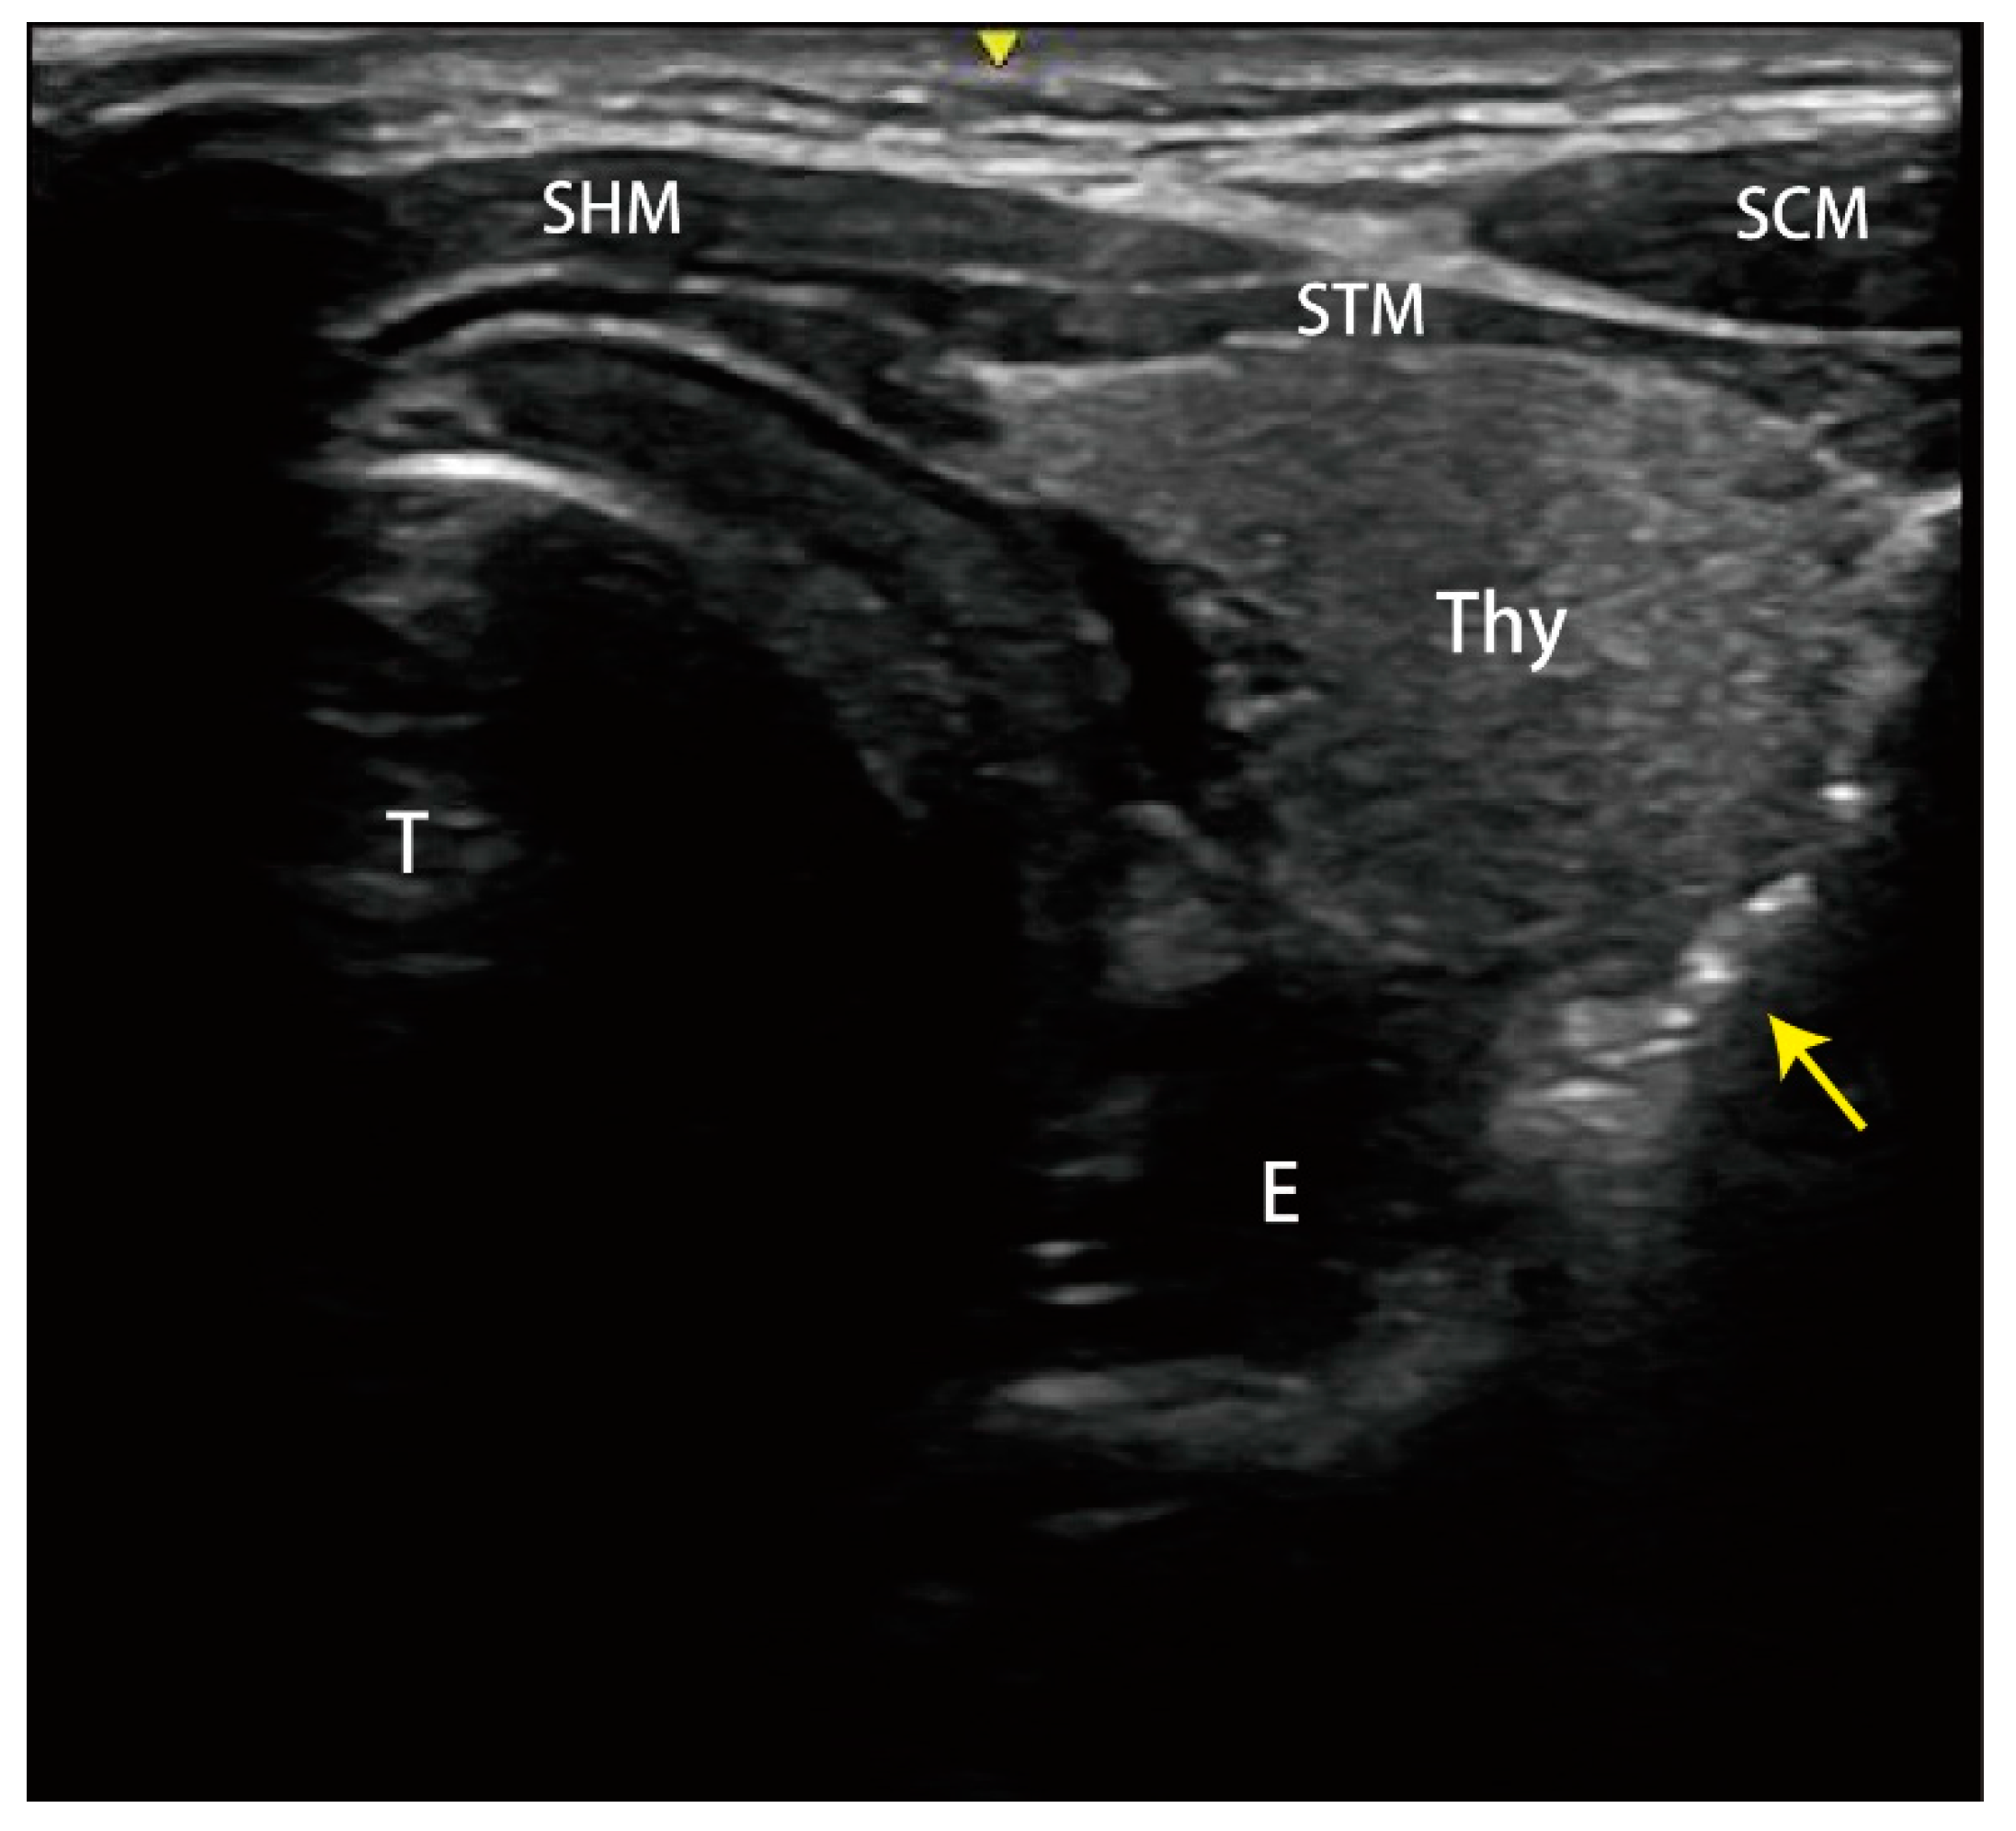

Figure 1.

Point-of-care ultrasound found the free air (yellow arrow) in the soft tissue of the neck with ring-down artifacts along the esophageal tract. STM: sternothyroid muscle; SHM: sternohyoid muscle; SCM: sternocleidomastoid muscle; E: esophagus; T: trachea; Thy: thyroid gland.